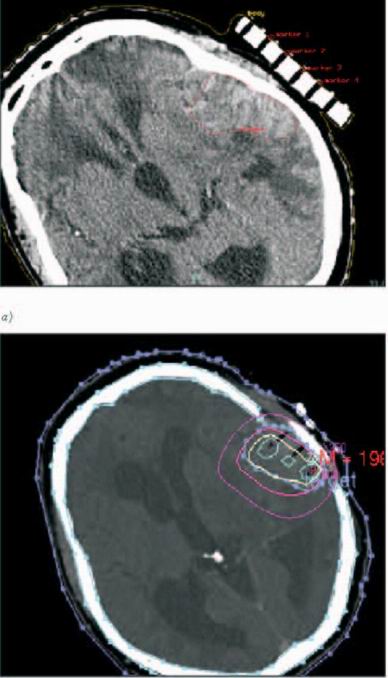

Brachyradioterapie

Jednou z možností cíleného ozáření reziduálních nádorů a recidiv

maligních gliomů (např. po předchozím zevním ozářením) v mozku je

použití stereotaktické intersticiální brachyradioterapie. Zdroje

HDR brachyradioterapie jsou speciálními aplikátory zavedeny přímo

do nádoru. Plánování radioterapie je nutné provádět trojrozměrným

plánovacím systémem za využití CT a MR snímků. Metodu lze za

určitých okolností považovat za alternativní řešení stereotaktické

radioterapie. Invazivní výkon je zatížen rizikem především infekce,

dále krvácením a rozsevem nádoru do dalších oblastí mozku. Celková

aplikovaná dávka 30-50Gy je rozložena do 3-4 dní s 2x denní

aplikací. Během aplikace se profylakticky podávají antibiotika a

antiepileptika.(obr. 7a, b)

Obr. 7: Intersticiální brachyradioterapie mozku: a) na fixační

masce připevněn vodící můstek pro aplikátory template, vyznačen

cílový objem; b) isodózní plán (izodózy 100%, 70%, 20%).